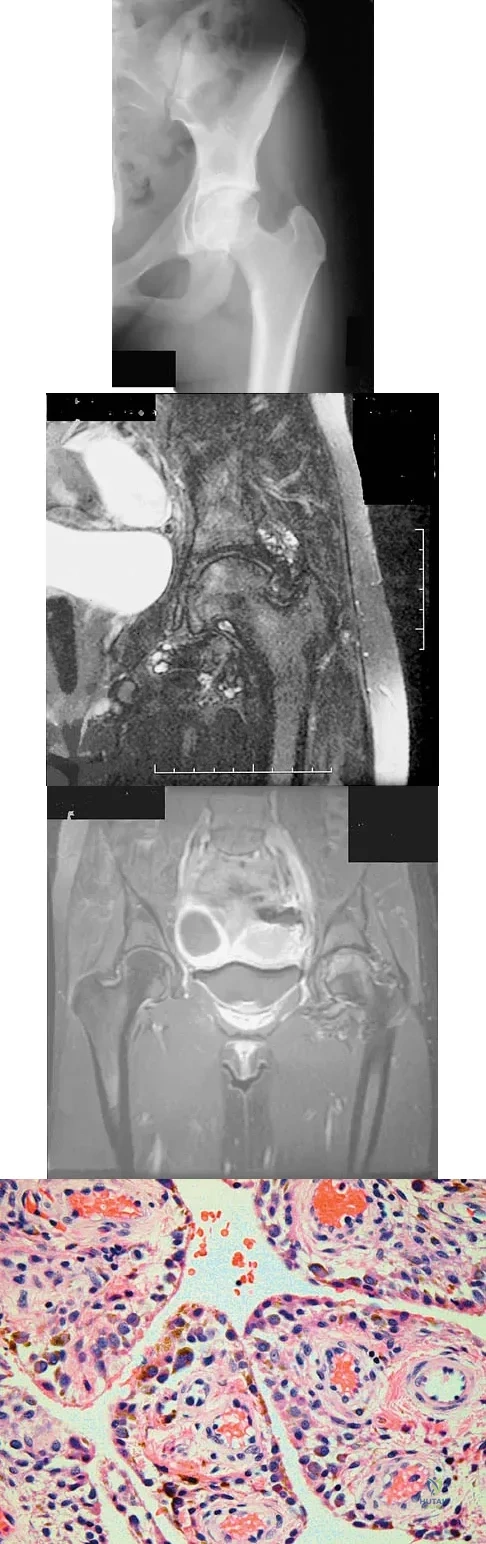

A 58-year-old woman has had a painless periscapular mass for the past year. An MRI scan and biopsy specimen are shown in Figures 4a and 4b. What is the most likely diagnosis?

Elastofibroma is a rare tumor that most commonly occurs in adults who are older than age 55 years. The lesions usually grow between the chest wall and the scapula, and 10% are bilateral. Histologic analysis shows that they are composed of equal amounts of elastin and collagen with occasional fibroblasts. Briccoli A, Casadei R, Di Renzo M, Favale L, Bacchini P, Bertoni F: Elastofibroma dorsi. Surg Today 2000;30:147-152.